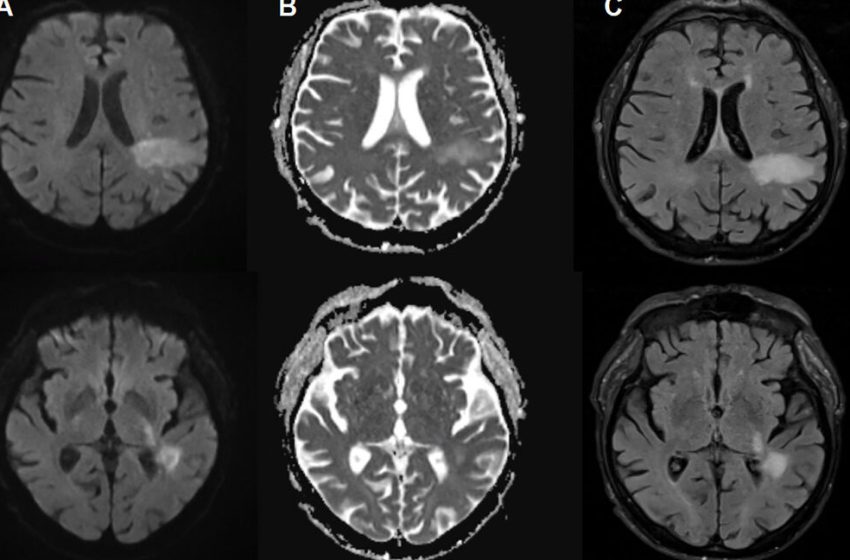

In PML, the new disease-causing virus or “PML-type” JC virus actively invades the brain, blowing up specific brain cells, including the cells that form the insulating myelin sheaths that protect nerve cells. This leads to extensive demyelination, which results in nerve cell dysfunction and death. On imaging, PML can show up as signature lesions in the brain. Those imaged lesions, paired with test findings of JC virus DNA in cerebrospinal fluid, are how PML is diagnosed. But for patients experiencing PML, the symptoms can mimic everything from a stroke to multiple sclerosis, causing problems like speech impairments, visual defects, motor dysfunction, and seizures.